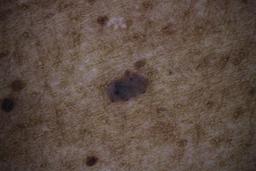

ISIC_6598546

Clinical

| Field | Value |

|---|---|

| age_approx | 60 |

| anatom_site_1 | Trunk |

| anatom_site_2 | Posterior trunk |

| concomitant_biopsy | False |

| dermoscopic_type | contact polarized |

| diagnosis_1 | Benign |

| diagnosis_confirm_type | single contributor clinical assessment |

| fitzpatrick_skin_type | VI |

| image_manipulation | instrument only |

| image_type | dermoscopic |

| lesion_id | IL_6711989 |

| patient_id | IP_8590441 |

| sex | male |